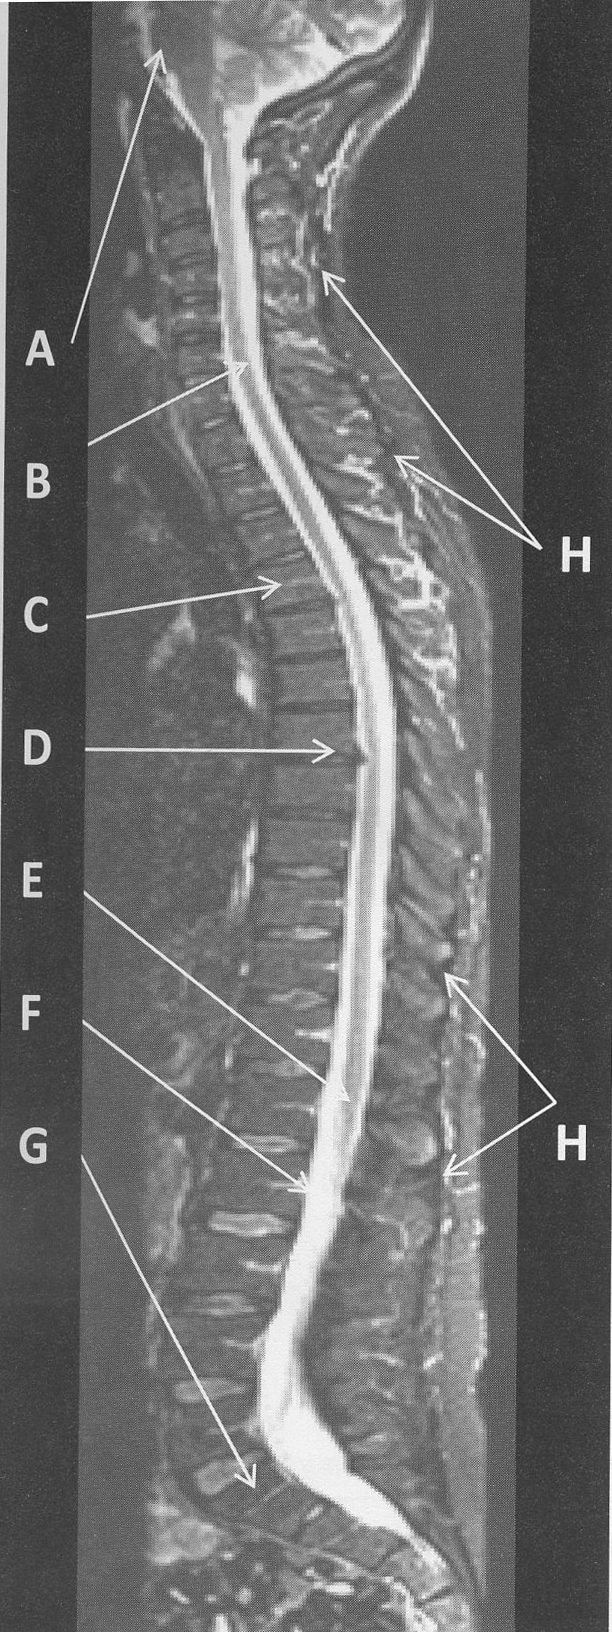

figure B 10 was acquiredin the _____plane

sagittal

figure B 10 is an example of a _____(weighting)

T1

figure B 10 arrow A

oropharynx

figure B 10 arrow B

anterior arch of C1

figure B 10 arrow C

Dens

figure B 10 arrow D

cervical disk

figure B 10 arrow E

trachea

figure B 10 arrow F

spinal cord

figure B 10 arrow G

vertebral body

figure B 10 the vertebral bodies of the C spine can be visualized because

hydrogen in cortical bone is too tightly bound to be “excited” by the MR process therefore cortical bone appears dark on MR images and outlines the vertebral body

bone marrow contains fat and water and therefore appears bright depending upon the scan parameters used to create the image

figure B 10 there is a slight cervical disk herniation at the level of

C5/C6